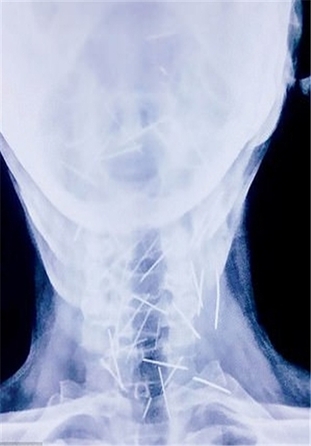

این مرد هندوستانی که «بادریلال مینا» نام دارد و در ایالت راجستان زندگی میکند، 75 سوزن در گردن، دستها و پاهایش وجود داشت.

بررسیها نشان داد حداقل 40 سوزن تنها در گلوی وی فرو رفته است که علت آن همچنان نامشخص است.